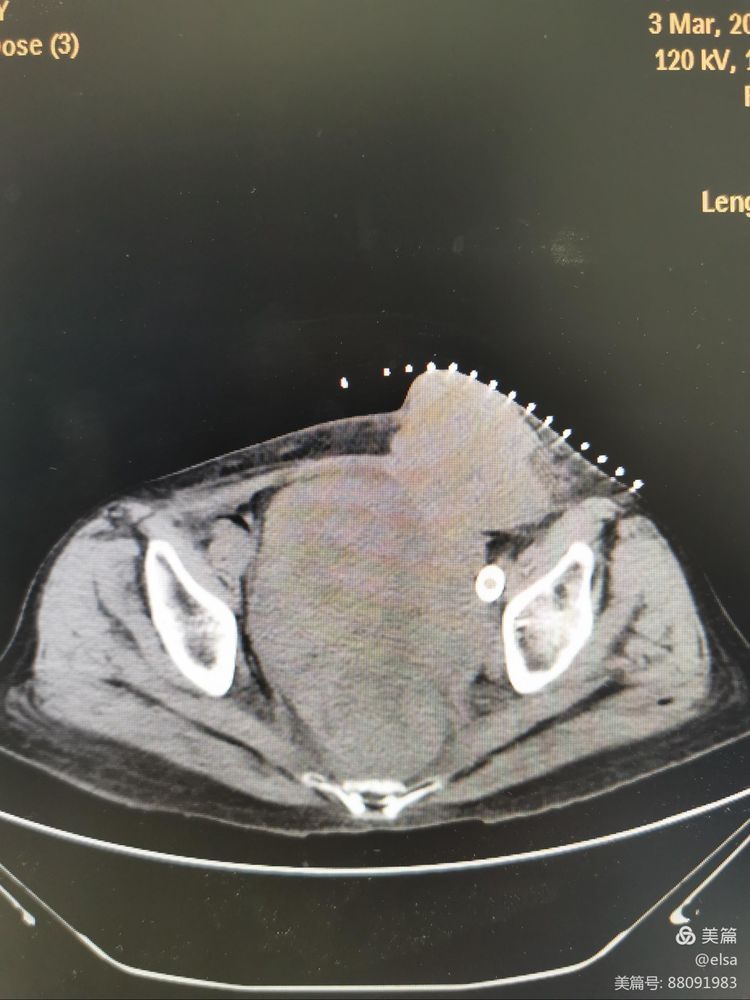

3月3日下午,血管介入科在CT引导下将微波针逐层穿入达肿瘤瘤体内部,连接消融穿刺针与微波消融机。接通冷循环管道及循环泵,根据术前讨论及定位图像,将消融功率定为:50W,消融时间定为10分钟进行消融治疗,消融结束后给予局部伤口包扎。

消融后立即复扫CT示:整个瘤体体积减小,肿瘤中心出现多个坏死区域,手术过程顺利。